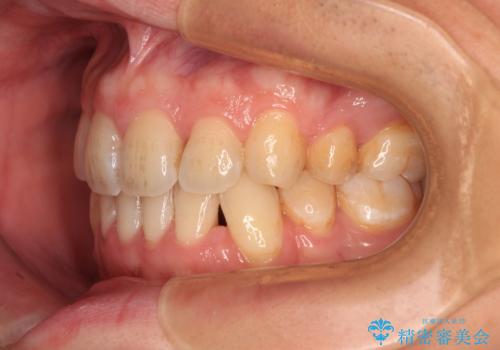

出っ歯と八重歯 目立たない裏側装置でスッキリとした口元に

- 上顎の前突感による口の閉じにくさと八重歯を気にして来院された患者様です。

目立たない装置を希望されたので、上顎が裏側装置のハーフリンガルを選択し、上下左右の小臼歯(計4歯)を抜歯して矯正治療を行うこととしました。

下顎骨が左側に大きく変位しているため、上下の正中位置は極力一致するところをゴールとしました。

上下顎で左右差の大きい抜歯矯正を裏側装置で行ったため、非常に時間がかかりましたが、正中位置も良い位置に改善され、気になっていた突出感も解消されました。